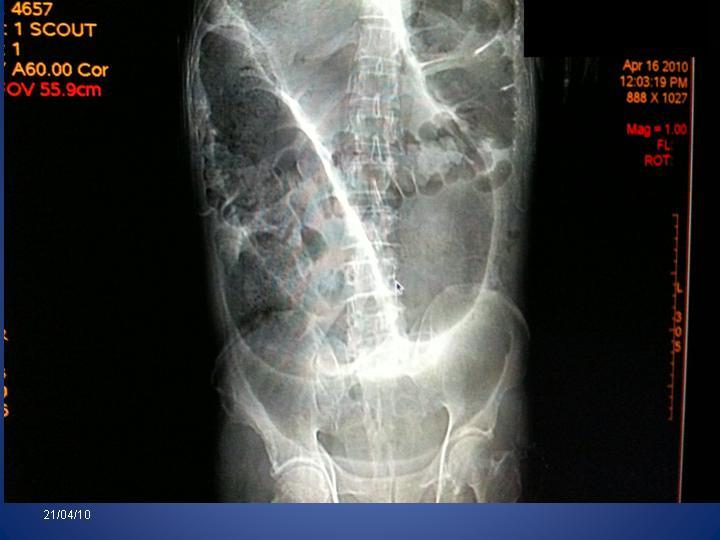

Vólvulo de Sigmoides

Coloproctología

| Autor: Francisco Suárez